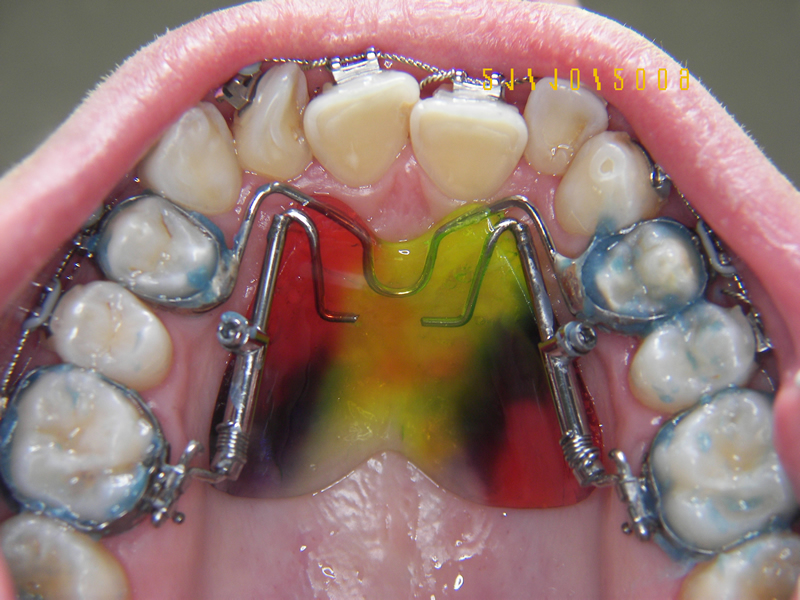

L'ortodonzia intercettiva include i trattamenti precoci (6-12 anni) con apparecchi mobili, funzionali, come attivatori, Frankel, Bionator, placche funzionalizzate e infinite altre.

Interveniamo sulla malocculusione in fase evolutiva, cercando di indirizzare la vettorialità di crescita, di ripristinare una normale funzionalità e modificare rapporti dentali anomali.

Personalmente ritengo questa la parte più affascinante dell'ortodonzia, ricordiamo il ruolo delle malocclusioni, dei dismorfismi cranio-facciali nel determinismo di cambiamenti di posizione cervico-scapolare.